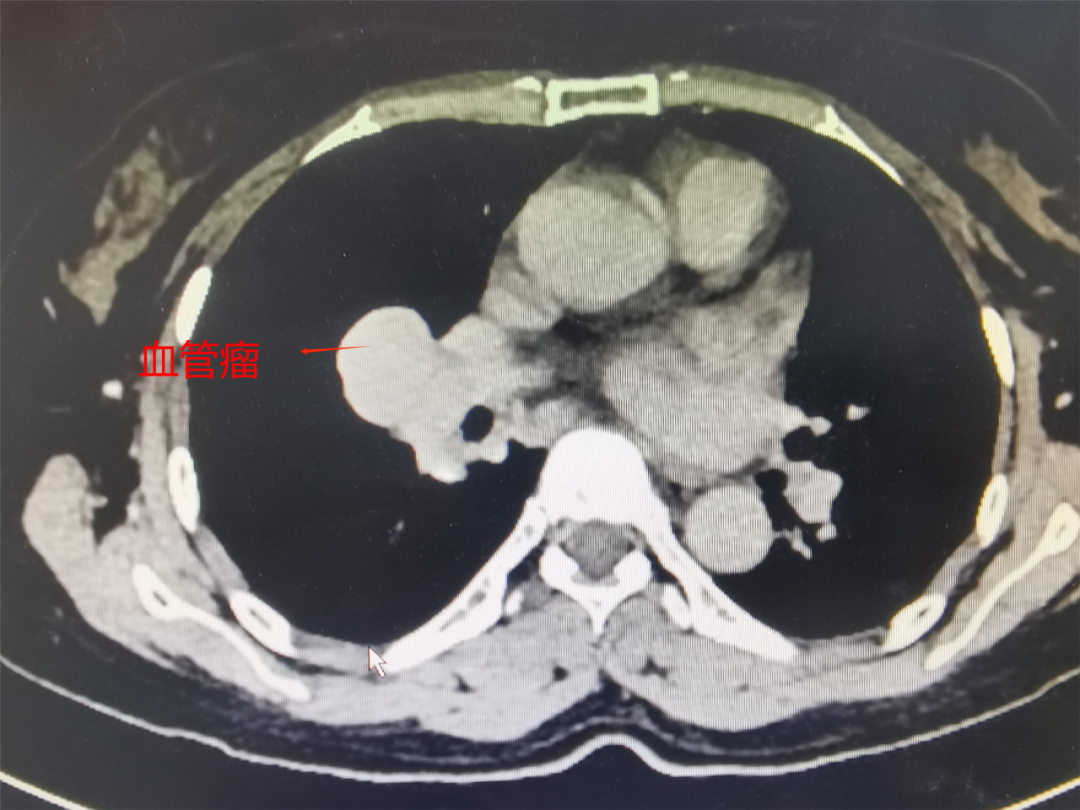

接下來(lái)這臺(tái)既復(fù)雜又考驗(yàn)技術(shù)的是極其罕見(jiàn)的血管瘤手術(shù),國(guó)內(nèi)鮮有報(bào)道。因血管變異且關(guān)系復(fù)雜,考慮到患者家庭經(jīng)濟(jì)壓力,沒(méi)有嘗試介入治療。由于腫瘤壁薄并位于血管根部,存在自發(fā)破裂的風(fēng)險(xiǎn),一旦破裂后,搶救成功率幾乎為零。該患者了解情況后夜不能寐,有強(qiáng)烈的手術(shù)意愿。曾主任通過(guò)術(shù)前仔細(xì)閱片,判定應(yīng)為靜脈瘤,主要血供來(lái)源于右下肺靜脈、右上肺靜脈及右中葉支氣管靜脈。

鑒于腫瘤位于中葉根部,與肺動(dòng)脈中間干及右中葉動(dòng)脈關(guān)系密切,血供極其豐富且壁又薄,故不能挖除,只能行右肺中葉切除術(shù)。該手術(shù)對(duì)動(dòng)作的精細(xì)度要求極高,一個(gè)微小的失誤就可能造成難以控制的大出血場(chǎng)面,危及患者生命。